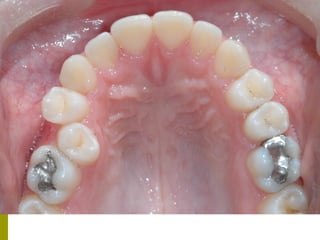

Προληπτικά μέτρα - Καλύψεις οπών και

σχισμών (ΚΟΣ)

 (Προληπτικές εμφράξεις, προστατευτικά, αποφράξεις οπών και

σχισμών, sealants)

   Οι μασητικές επιφάνειες των οπισθίων δοντιών

ευνοούν την κατακράτηση τροφών και μικροβίων και

συχνά τερηδονίζονται αμέσως μετά την ανατολή τους.

   Έρευνα της Ελληνικής Οδοντιατρικής Ομοσπονδίας

έδειξε ότι σε παιδιά ηλικίας 12 ετών το 83% των

τερηδονισμένων επιφανειών παρατηρείται στις

μασητικές επιφάνειες      (Ουλής Κ.Ι. συν. Ελληνικά

Στοματολογικά Χρονικά 2009’ 53(3)΄97-120)

   Επίσης και μετά από παρακολούθηση έως 10 - 15 έτη, μόνο

το 30 -40% των δοντιών με κάλυψη είχαν μασητικές

αποκαταστάσεις, σε σχέση με 60 -80% των δοντιών χωρίς

καλύψεις.

   Μελέτες έχουν δείξει μείωση της τερηδόνας ,μετά την

τοποθέτηση ΚΟΣ, 85 -37 % μετά από 2 – 6 έτη

    οι προληπτικές καλύψεις θα πρέπει να εφαρμόζονται

ανάλογα με τον βαθμό κινδύνου ανάπτυξης τερηδόνας των

ατόμων, ή των επιφανειών επιλεκτικά και εξατομηκευμένα